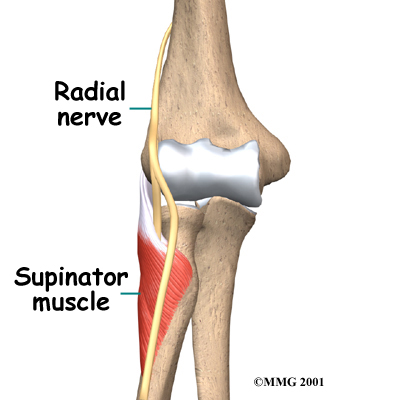

On the lateral part of the elbow, the radial nerve enters a tunnel formed by muscles and bone. This is called the .

Passing through the radial tunnel, the radial nerve runs below the . The supinator muscle lets you twist your right hand clockwise. This is the motion of using a screwdriver to tighten a screw.

After the radial nerve passes under the supinator muscle, it branches out and attaches to the muscles on the back of the forearm.